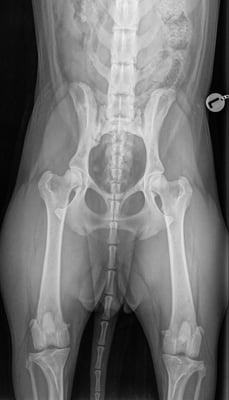

Lahmheitsuntersuchungen

Untersuchung und Abklärung von Lahmheiten

digitale Röntgenuntersuchung in der Praxis

Erstellen von HD und ED Röntgen für die offizielle Auswertung